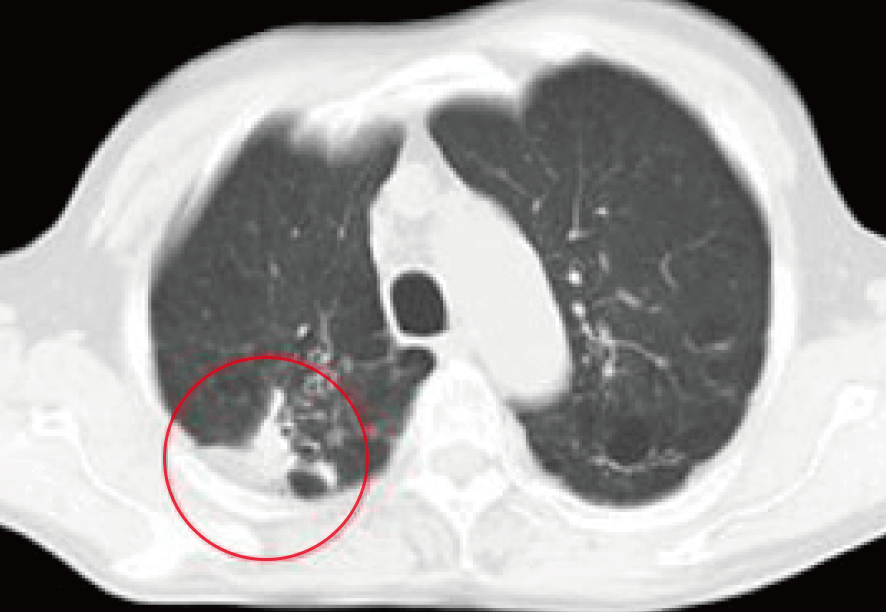

治療前CTでは右肺の背面に原発性の肺がんと、その周囲のろっ骨浸潤が認められた。

提示した治療後の写真は半年経過時点の胸部CT写真である。

各種免疫検査によって異常な免疫状態の発見と改善が行われなければ、非常に厳しい予後を招いたケースである。

今後は再発や転移の無きよう、定期的な経過観察を指示した。